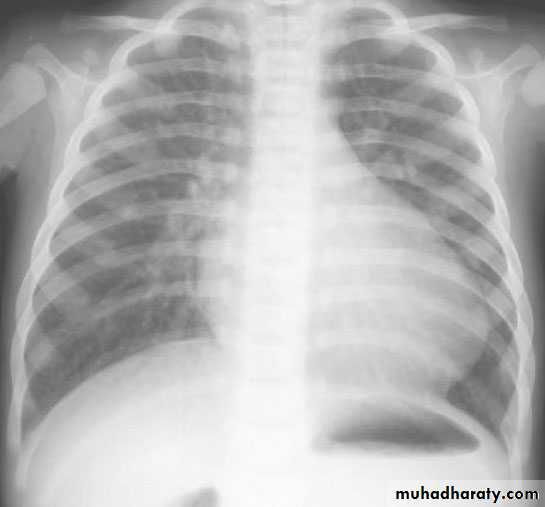

• Cardiomegaly, rib notching on X-ray.

notching of ribs in

coarctation.• Treatment